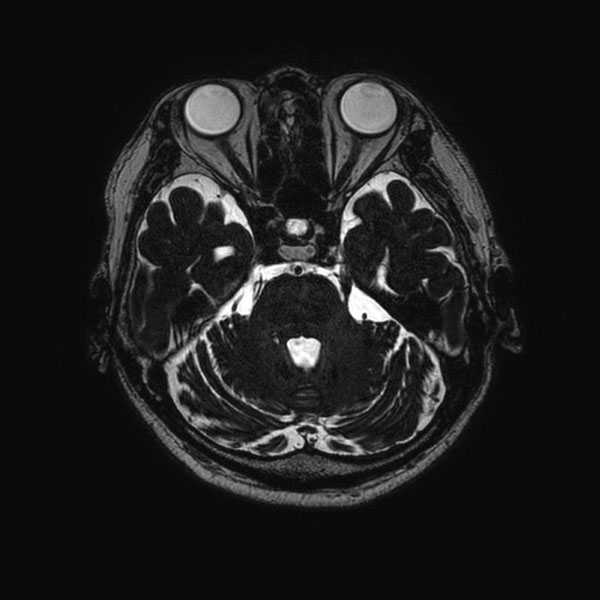

578

'26年2月

60代

右三叉神経痛

減圧前

減圧後